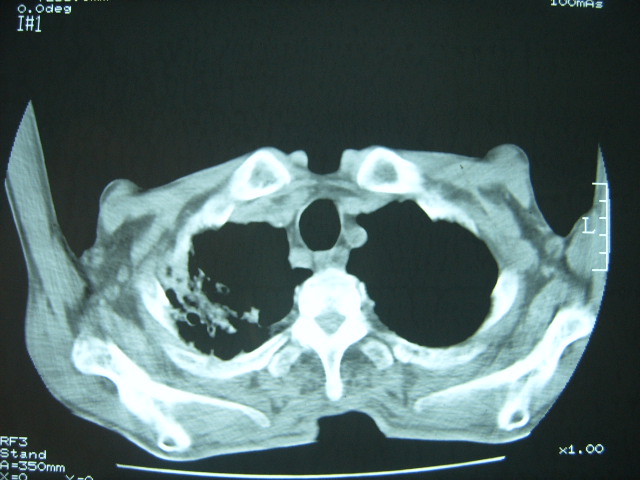

男74岁,咳嗽,寒战,低烧。有糖尿病史。

两肺结核,空洞形成,左下肺肺段隔离症待排

1、陈旧性肺结核

2、左下肺脓肿